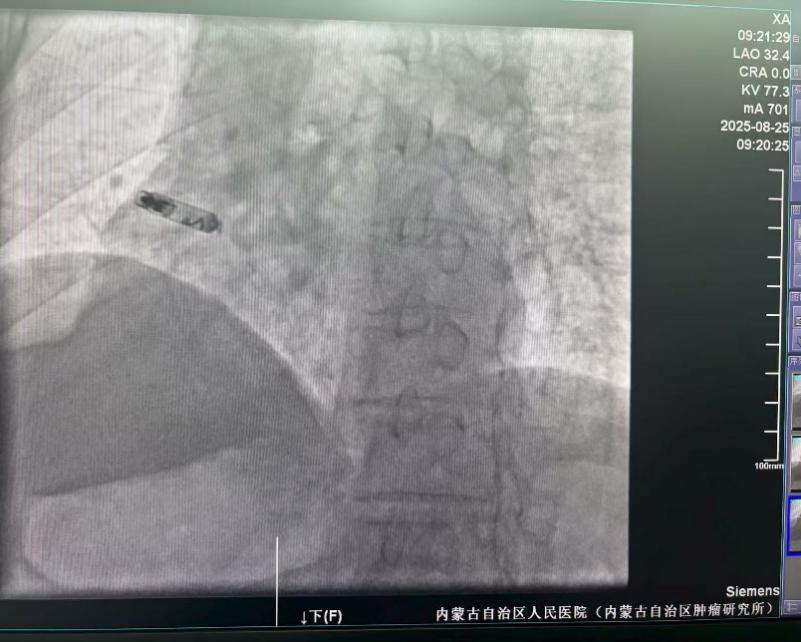

手术团队通过患者股静脉这一微创路径,将仅有传统起搏器十分之一大小的新型无导线起搏器精准输送至右心耳,利用其特有的用于心房起搏的双螺旋设计,起搏器被牢固地锚定在右心耳基底部。整个手术过程顺利,耗时22分钟,术中及术后参数测试均显示起搏器工作状态良好。

LAO 30°造影,确保导管与组织接触,并贴靠心耳基底部。